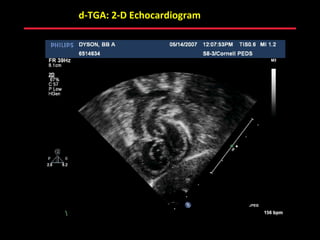

d-TGA: 2-D Echocardiogram

ABB MD